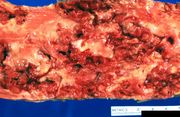

| 21:43, 20 August 2013 | IPLab6MM4.jpg (file) | 47 KB | This is a photograph of the vertebral column from this patient at autopsy. Notice the collapsed vertebra (1). There are multiple variably-sized white nodules (2) within the bone marrow. These are accumulations of malignant plasma cells in this case of ... | 1 | |